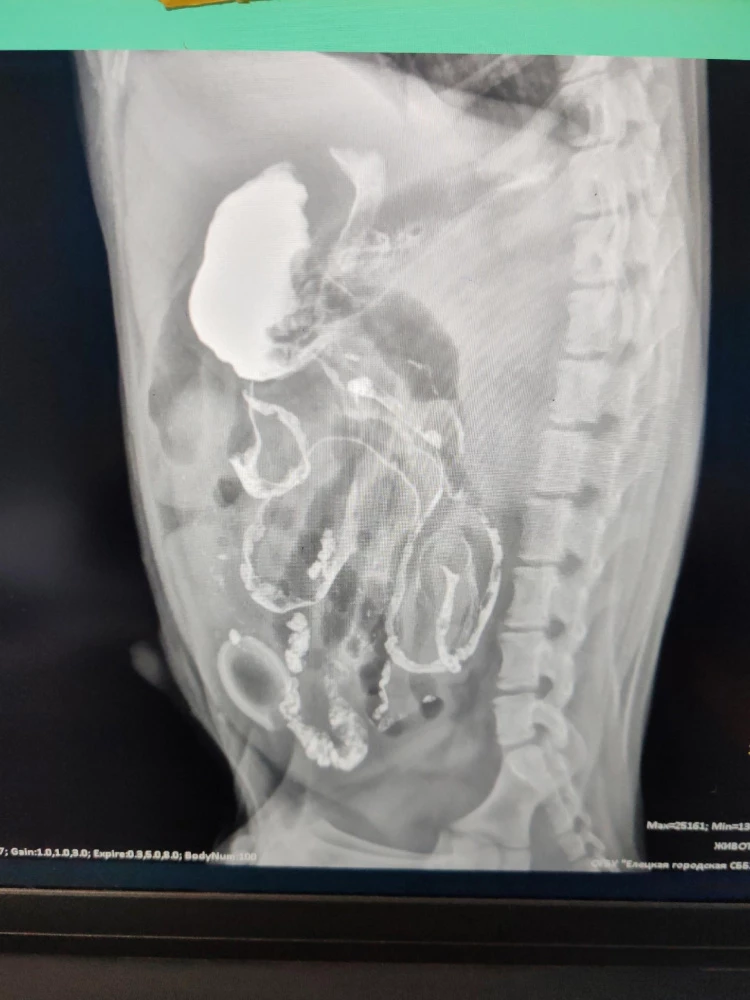

Как сообщает управление ветеринарии Липецкой области, ветеринарный врач обнаружил уплотнение в тонком кишечнике. А рентген с контрастом показал инородное тело округлой формы, похожее на часть детской соски. Хозяйка подтвердила, что щенок недавно играл с соской и мог её проглотить.

17 марта провели повторный рентген. При этом владельцы продолжали давать щенку контрастное вещество, и часть соски вышла естественным путём.